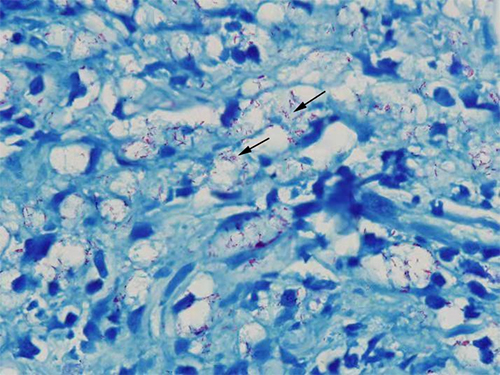

麻风患者皮肤组织病理抗酸染色图片(1000X),图中红色的菌团就是麻风菌

麻风病是由麻风分支杆菌引起的慢性感染性疾病,主要感染皮肤、外周神经、眼等器官。1873年2月28日,挪威科学家汉森在麻风患者的淋巴结中发现麻风分枝杆菌,因此,麻风病也称为汉森氏病。